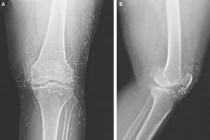

| Người phụ nữ Hàn Quốc, 65 tuổi, đã có hàng trăm kim châm cứu nhỏ trong mô đầu gối. Người ta cho rằng chúng được cố ý bỏ lại bởi chuyên gia châm cứu đang điều trị viêm xương khớp cho bà. |